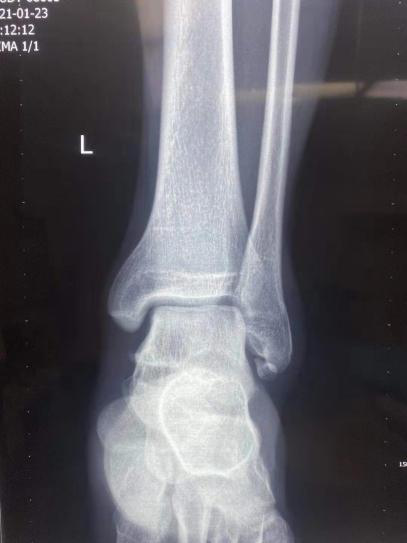

近期,我院骨科四病区刘京升主任团队积极进行学科内交叉合作,在踝关节扭伤导致的慢性踝关节不稳诊治方面积累了丰富经验,进一步推动了省内足踝外科的发展。

科室副主任医师王凯查阅大量文献,总结既往踝关节反复扭伤的典型病例特点,并对多例病例进行随访,发现人工韧带结构在治疗慢性踝关节不稳的中远期效果与传统踝关节外侧副韧带重建手术效果相当,但是手术步骤及手术时间大大缩减,术后并发症明显减少,同时患者生活质量明显提高。

既往,对慢性踝关节不稳的治疗主要采用非手术保守治疗或非解剖学重建手术治疗,即利用部分腓骨短肌腱穿过腓骨远端骨道,配合锚钉加强固定来重建踝关节外侧韧带的手术。但传统术式需要牺牲一条腓骨短肌腱,术后导致足的外翻肌力减弱,同时受移植肌腱长度的限制,有时不能很好地通过多次折返缠绕来达到非解剖重建的目的,从而造成行该手术的患者远期恢复效果不理想。

目前,骨科四病区通过人工韧带结构治疗慢性踝关节不稳,遵循等长收缩的原理,更符合踝关节生物力学的特点,术后不限制后足的活动,既没有破坏受损踝关节周围的正常组织,而且由于人工韧带结构强度高,又能有效的保证术后踝关节的稳定性,远期效果显著。此手术方式可有效地改善患者踝关节的功能,减轻其术后疼痛的程度,促进患者康复,值得后期推广应用。